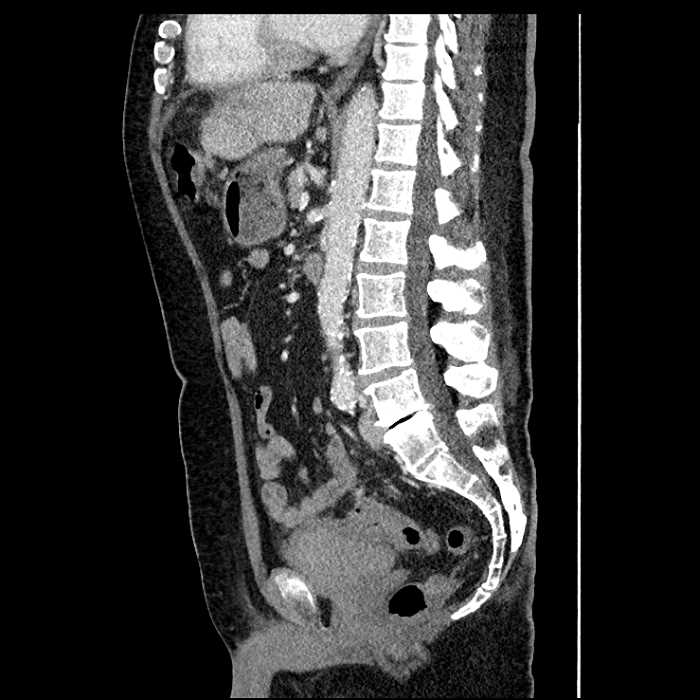

Age: 63

Sex: Male

Indication: Abdominal pain

• Mild mural thickening of a segment of the sigmoid colon with adjacent fat stranding and a 1.5 cm fluid and gas collection along the tip of an inflamed diverticulum

• Loss of the normal fat plane between this collection and adjacent loops of small bowel, which demonstrate mural thickening

• No bowel obstruction

Acute sigmoid diverticulitis complicated by a small contained perforation and a large abscess in the right hepatic lobe. Additional small subcapsular abscesses along the anterior margin of the left hepatic lobe.

Additionally, loss of the normal fat plane between the peridiverticular collection and adjacent thickened loops of small bowel raises the potential for an enterocolonic fistula.

Hepatic abscess showing the double target sign with low density internally surrounded by a thin inner enhancing rim (red arrow) and ill-defined outer low density rim (yellow arrow). Blue arrow indicates an internal septation. Red arrows: additional smaller subcapsular abscesses. Red arrow: focal contained perforation associated with diverticulitis.